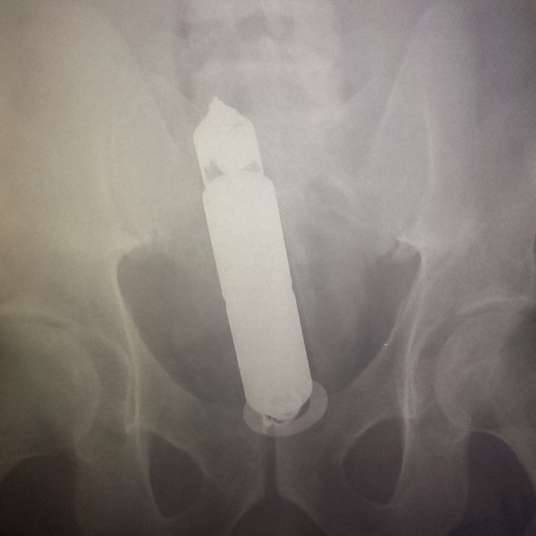

做完X光检查后,他们发现按摩棒卡在女友的直肠里,已经横了过来。那位帮女友治疗的医生是出了名的大嘴巴,这件事很快就会传遍整个医院,他们以后该怎幺在这里工作?床上的小情趣变成整间医院的笑谈,这对情侣真是太倒霉了。分享出去,让更多人看到这件趣事吧。